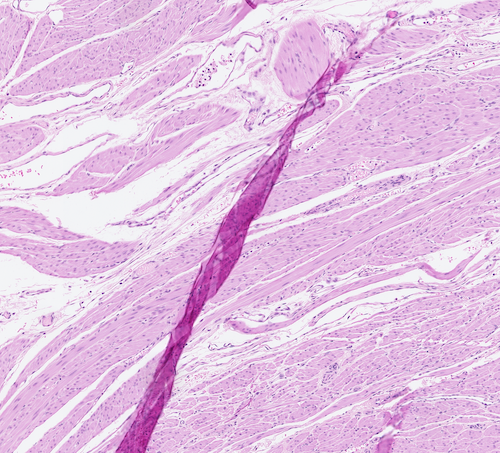

Regardless whether we use digitization or microscopy, the presence of artifacts such as folded tissue might negatively affect the diagnosis [4]. When digital technology is used other artifacts like blur may also reduce the quality of computerized algorithms [10]. Tissue fold can occur in the sectioning part of tissue processing when a thin tissue slice is folded [11]. Figure 1 shows three samples of folded tissue.

[5pt] \stackunder[5pt]

\stackunder[5pt] \stackunder[5pt]

\stackunder[5pt]